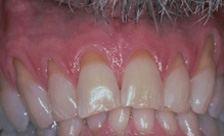

Case #1

| BEFORE | AFTER |